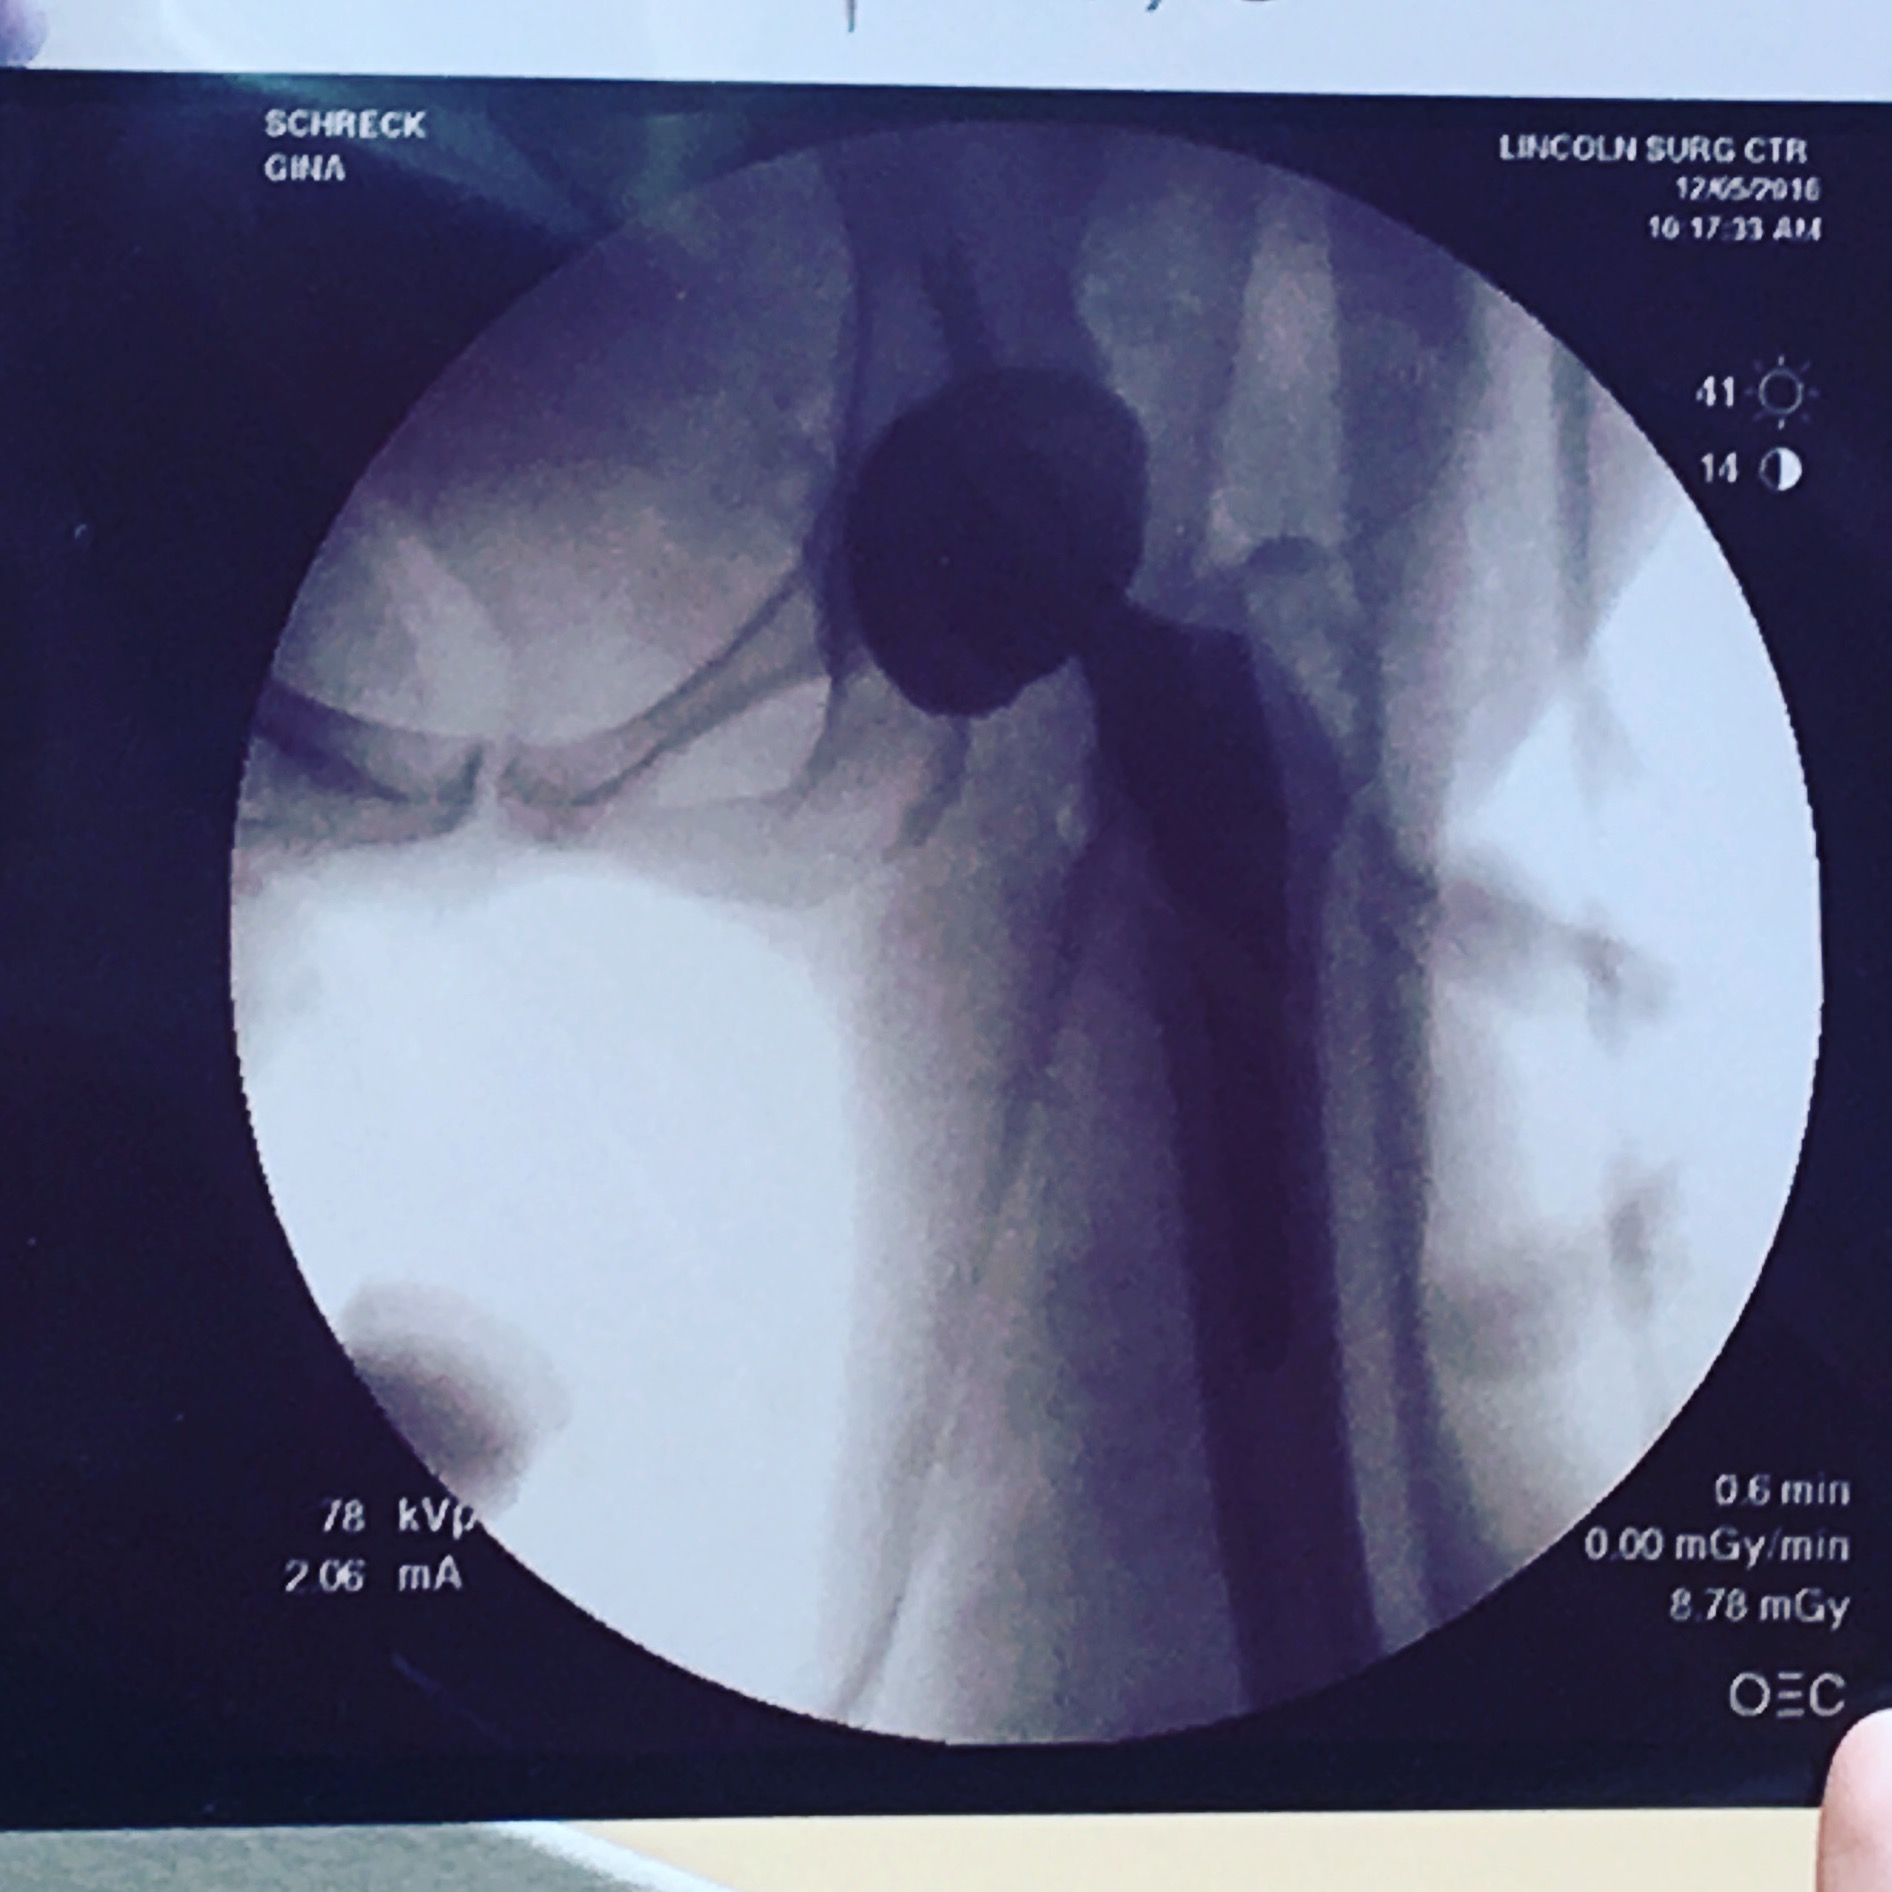

13 days ago I had a hip-replacement surgery, which I am choosing to call my first bionic surgery. It has nothing to do with aging or arthritis, but instead the assimilation of the super-robot body I will have in a few years. I had heard that today’s hip surgeries were quite remarkable and the recovery was only a few weeks. My surgeon said I didn’t even have to spend the night, unless I was experiencing extreme pain, in which case, I could stay one night.